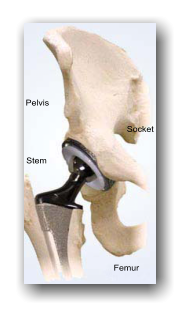

Pelvis Stem Socket Femur